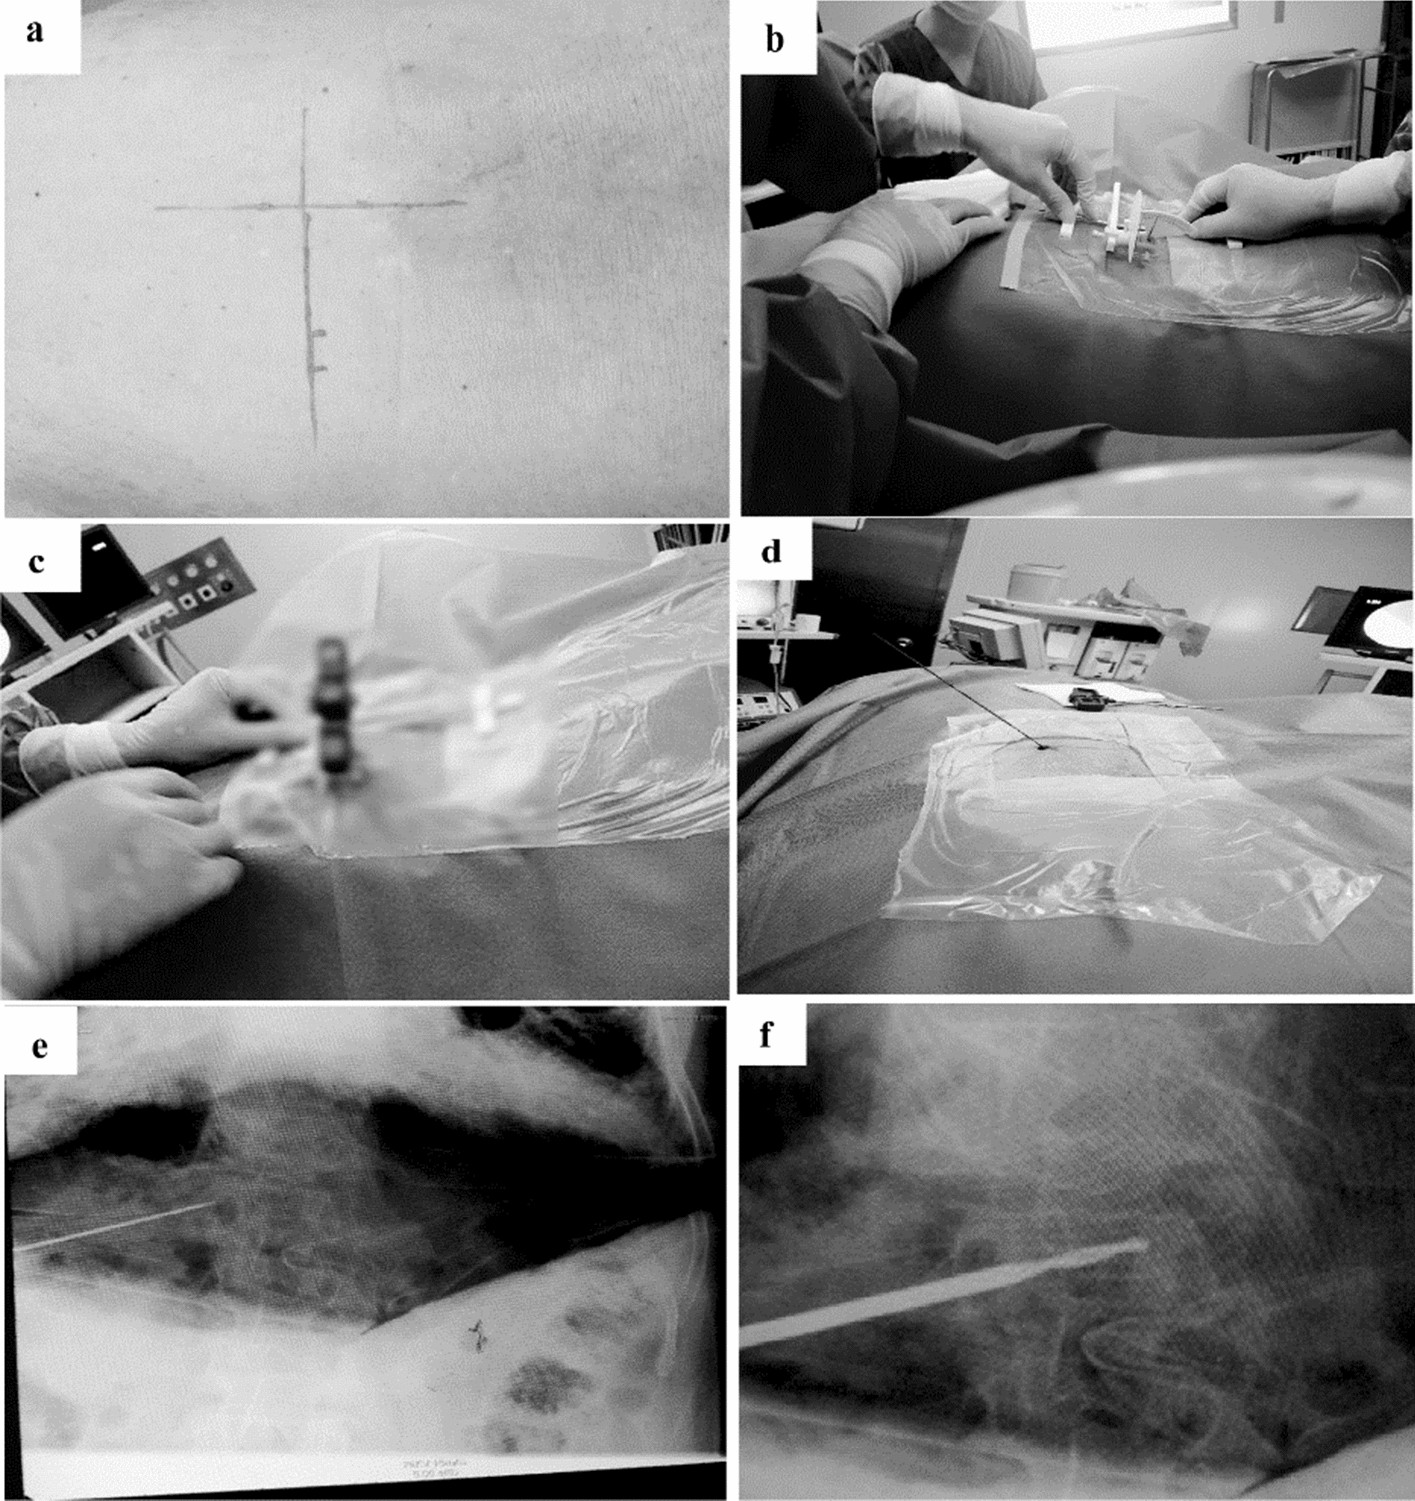

Figure 4

From: Application of a new percutaneous multi-function pedicle locator in minimally invasive spine surgery

Percutaneous kyphoplasty by using the locator. Graph (a) shows that the patient was in the prone position. ML and HL lines, as well as the percutaneous puncture point “P” were marked according to the data acquired from the images preoperatively. Graph (b) illustrates that the locator was placed parallel to the ML line after adjusting for the positions of the hands on dials at the defined angles according to the preoperative measurement of extraversion angle α- and tail tilt angles β. Graphs (c) and (d) display that a cannula was placed in the locator, making the distal end of the cannula aligned with the puncture point “P”, and then, a guide needle was inserted into the cannula until the pedicle bone puncture point was planted into the pedicle. Graph (e) shows that the position of guide needle was confirmed by 2D fluoroscopy. Graph (f) depicts that a saccule was placed through the working channel and the fractured vertebral body was expanded with an appropriate pressure. Then, bone cement was injected into fractured vertebrae to stabilize the spine and relieve pain.